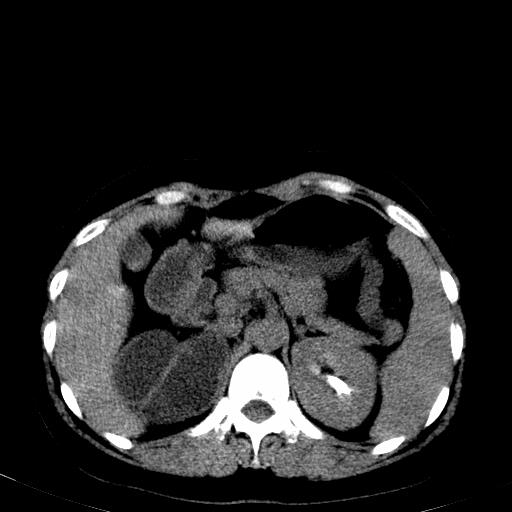

患者体检发现右肾体积增大,怀疑右肾积水

右肾重度积水,以肾盏积水明显,有分隔,上段输尿管轻度扩张,管壁增厚,考虑肾结核可能,请结合尿检查,胸部拍片排除肺结核。

右肾重度积水,建议ct向下扫描或逆行造影,左肾及左输尿管结石 .

右侧肾积水、左侧肾结石 ,原因待查

1)不排除右肾结核可能。2)左肾及左输尿管上段结石?